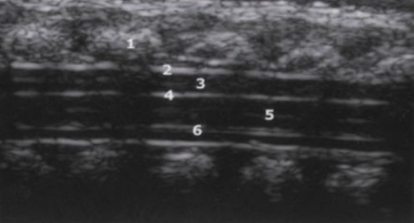

1

subarachnoid space

2

cartilaginous spinous processes

3

dura mater

4

epidural space

5

central echo complex in hypoechoic spinal cord

6

conus medullaris